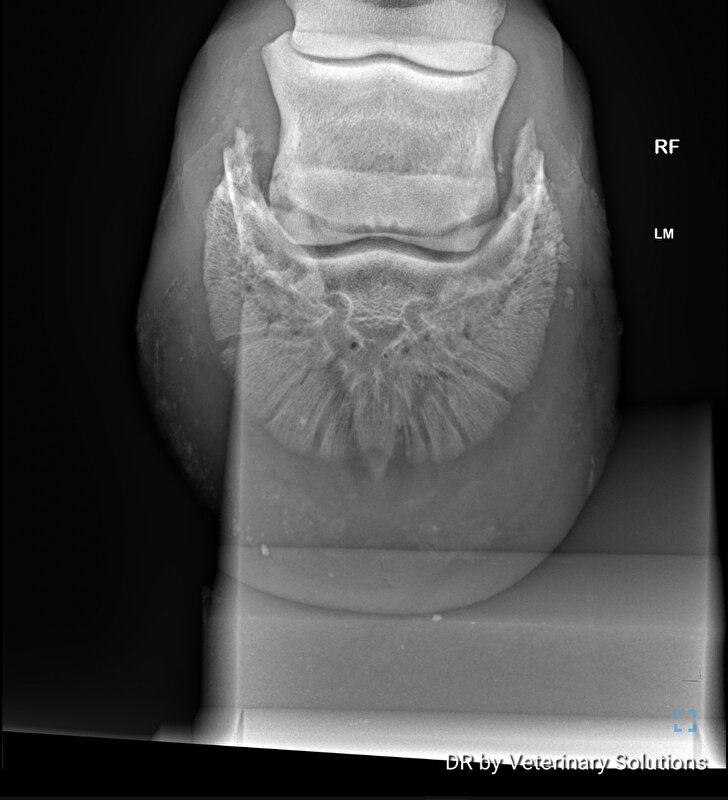

zefiros schreef:Hier best erge verbening vh hoefkraakbeen beide hoeven.